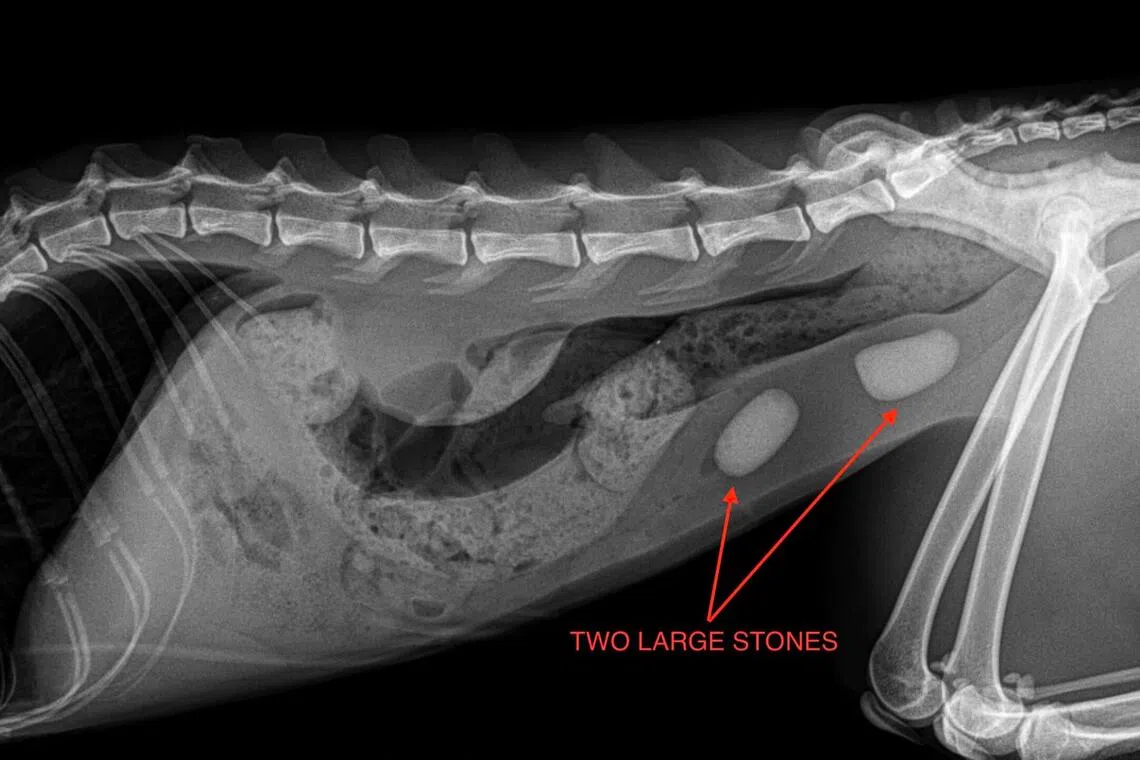

X-ray of two large bladder stones.

PHOTO: WESTSIDE VETERINARY EMERGENCY AND REFERRAL HOSPITAL